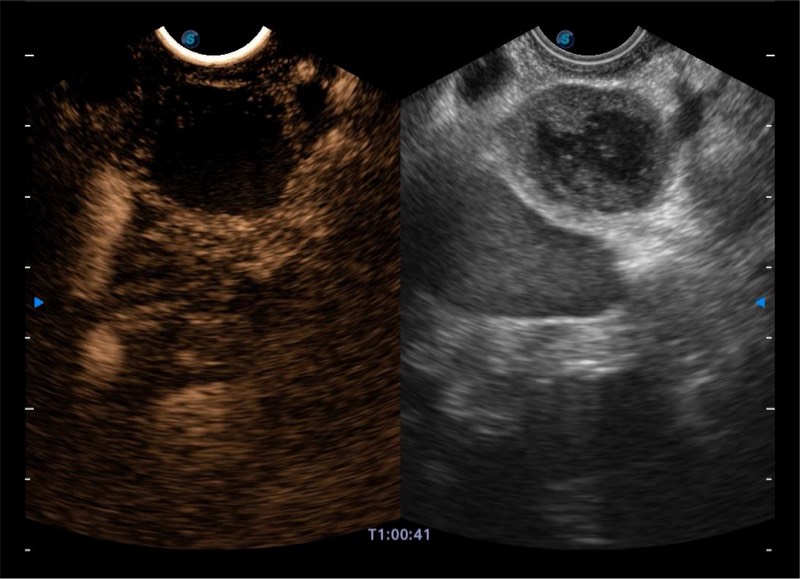

高端超声影像平台

基于二十年的超声技术积累,竞技宝(JJB)官方网站提供了最新一代的独立超声主机,在提供高质量图像的同时满足多学科使用。具备常见多普勒技术并提供弹性成像、声学造影等高端影像技术。新一代传感器具有更强的抗干扰能力并减少图像伪影。